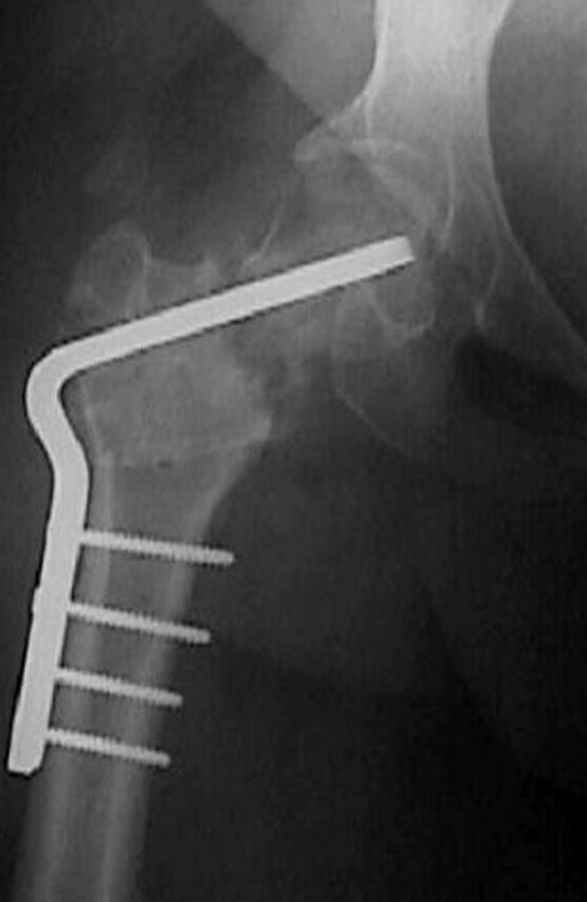

5:24 Рентгенограмма таза, вызывают врача ортопеда (снимок N1), его диагноз: закрытый переломо-вывих правого тазабедренного сустава, получает добро на закрытую репозицию в приемном отделении

N 2

7:30 начало операции, больной на спине, попытка репозиции после анестезии N3, укладка больного на боку, доступ Kocher- Langenbeck, состояние седалищнего нерва около 2.5см кровоподтек, через joistick головка бедра приподнята, освобовождение сустава, фрагмент заднего края более 3х4 см репонирован на свое место. После промывания

сустава, репозиция вывиха (N4), фиксация фрагмента 2.7(4) мм шурупами и допольнительно реконструктивной пластиной на 8 дырок, фиксация 3.5мм шурупами проксимально и дистально.

Интраоперционные N5 косая запирательная и N6 подвздошный снимок

11:50 больной в послеоперационной, рентгенограмма N7, компьютерная томограмма в тот же день N8-10

На рисунке N1 предоперационный план лечения ложного сустава шейки бедра- линия ложного сустава, угол и направление введения импланта, клиновидная остеотомия в градусах и миллиметрах, второй снимок после коррекции, расчет, на сколько удлиняется конечность и размеры импланта;

N3 рисунок окончательный снимок, после операции моя рентгенограмма должен выглядеть примерно как эта картина. На N4 снимке клин перед удалением; N5 послеоперации 3 нед.; N6 окончательная рентгенограмма.

варус при проксимальном отделе 95 градусной пластиной.